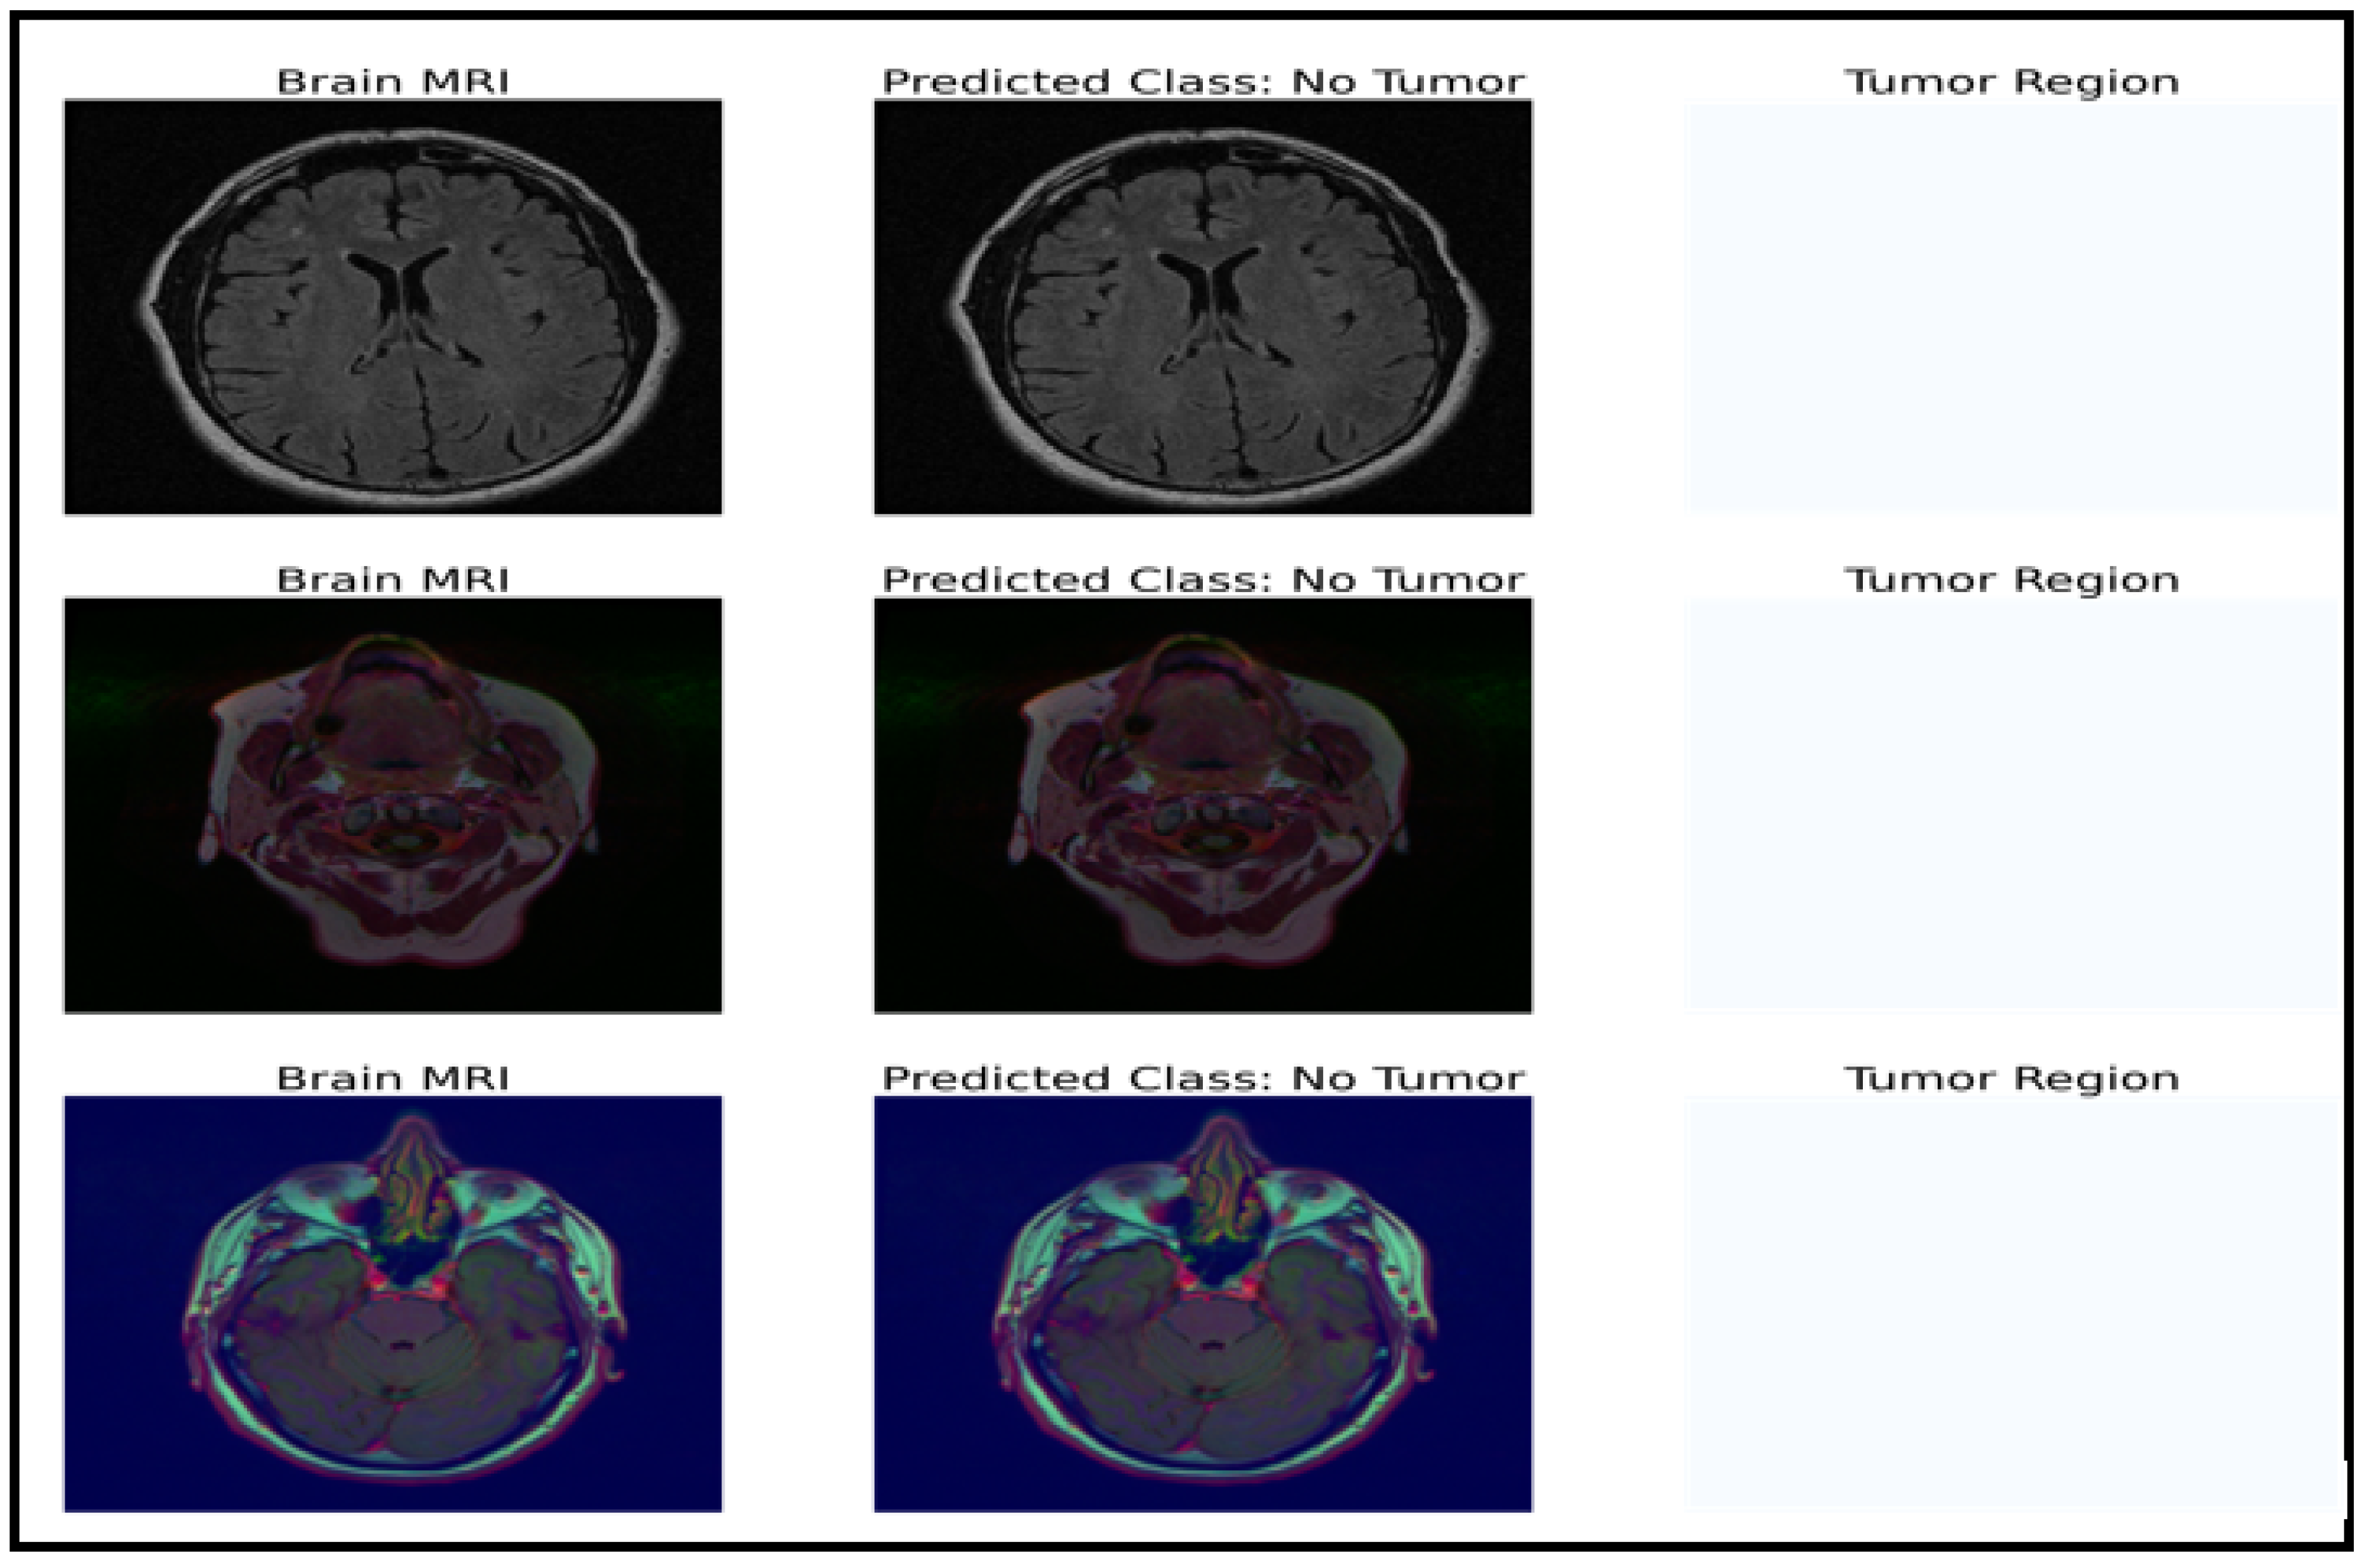

The model can be used for brain tumor segmentation. The result of the U-Net architecture is a probability map representing the likelihood of each pixel in the input image belonging to the tumor region. A threshold can be set on this map to obtain the binary segmentation map, which indicates the presence or absence of the tumor in each pixel of the input image. The binary segmentation map obtained from the U-Net can be used to improve the accuracy of the brain tumor detection and classification tasks performed by the CNN model with fine-tuned ResNet50. For example, the binary segmentation map can focus the proposed model’s attention on the tumor region, reducing false positives and improving the overall accuracy. To integrate the outputs from the CNN model with fine-tuned ResNet50 and the U-Net architecture, the binary segmentation map can be overlaid onto the input MRI image to highlight the tumor region. Figure 7 shows the segmentation results for a selected tumor region, while Figure 8 shows the results for a non-tumor region. This combined approach can provide valuable insights for clinical diagnosis and treatment planning.

Figure 7.

Dataset classification and model prediction of tumor regions.

Figure 8.

Dataset classification and model prediction of no-tumor regions.